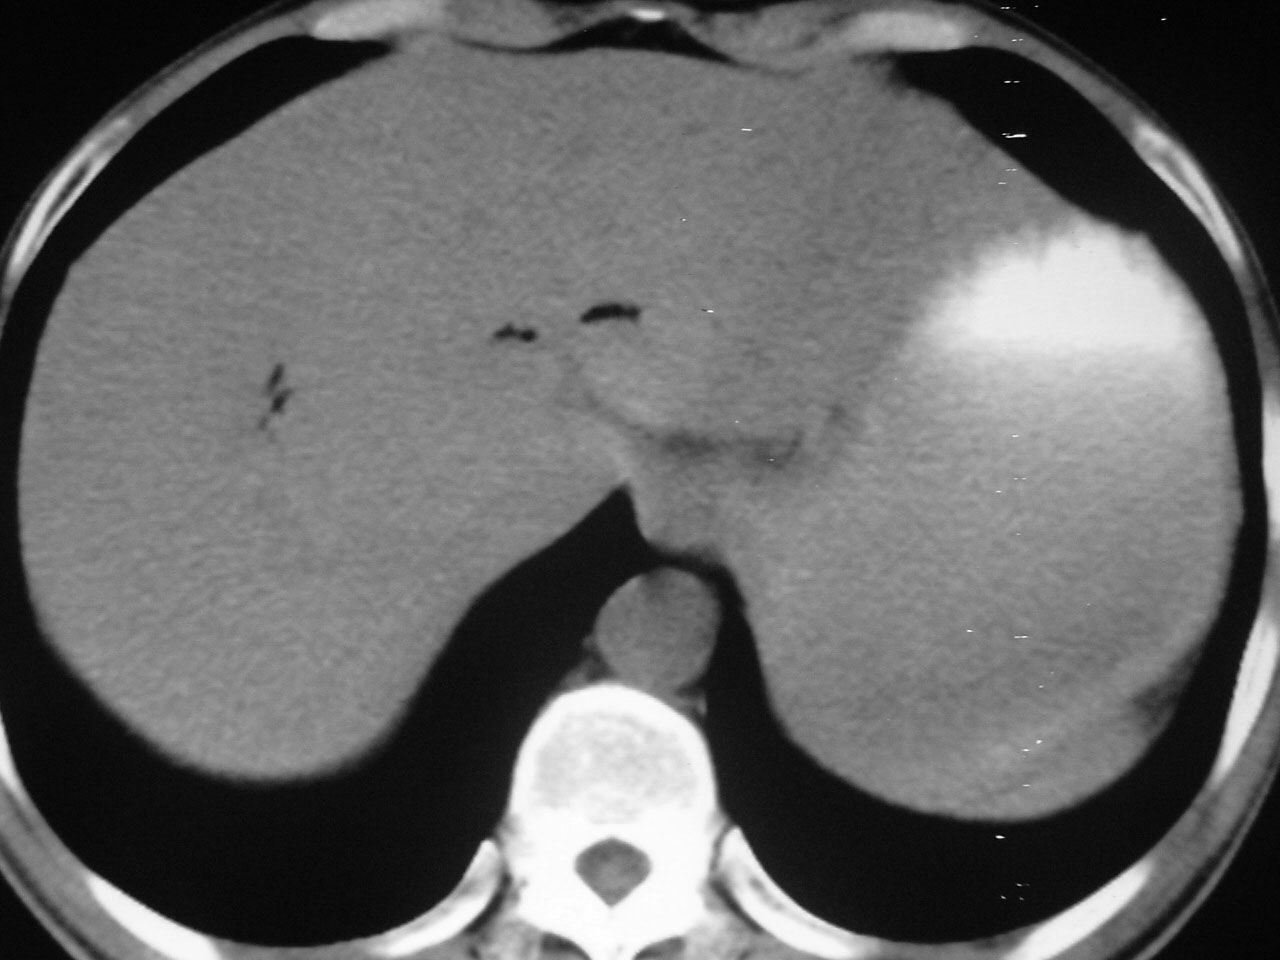

m/52y,右上腹疼痛一天,体温39度,wbc一万多。黄疸。

胆道感染产气

急性胆囊炎。胆道感染所致。

急性胆系感染所致,胆囊增大.

胆囊周围的气体是肠道内的。

又有临床又有影像胆道产气菌感染诊断明确。

肝内外胆管内积气扩张,密度不均匀,结合病史及血像所见考虑为化脓性胆管炎(产气杆菌所致).

胆管炎引起积气也不是太少见,支持!